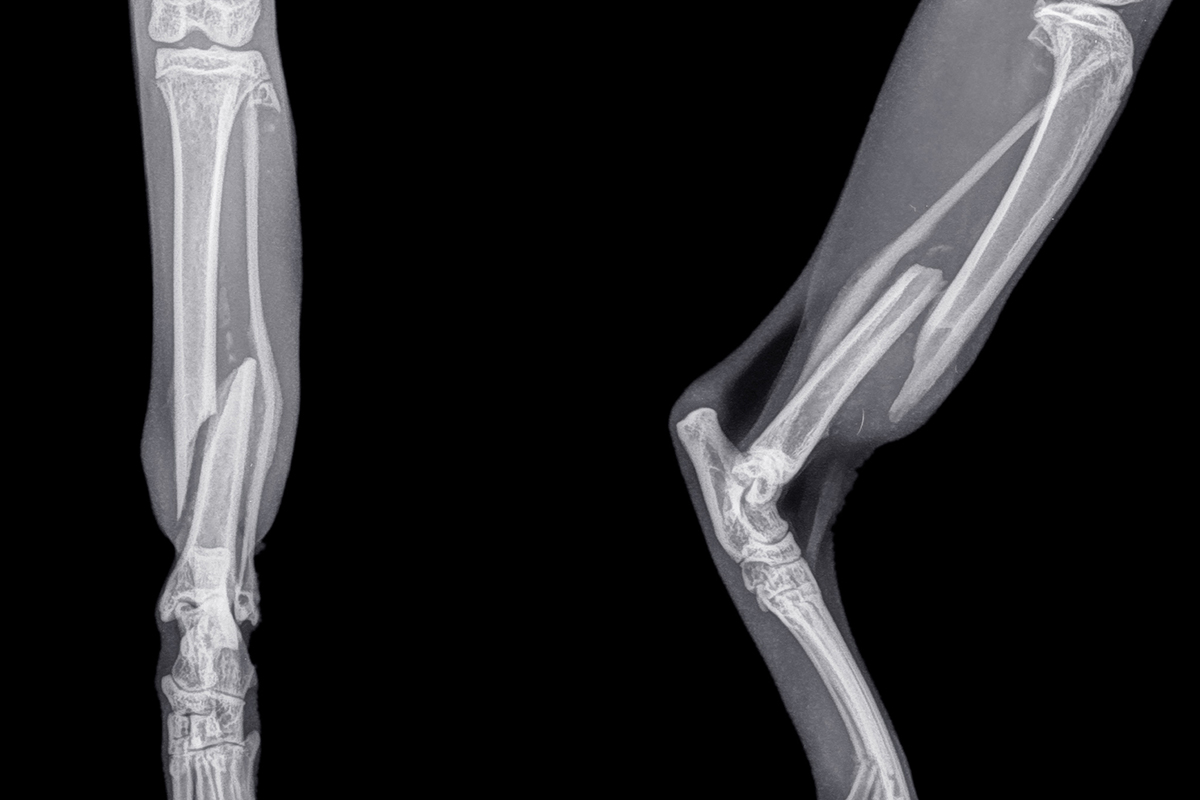

골절 치료

골절의 형태와 상태에 따라 치료 방향이 달라집니다

골절 단계별 진행 상태

1단계

보행 상태 및 통증 반응 평가

2단계

X-ray를 통한 골절 형태·정렬 분석

3단계

아이의 나이·체중·활동량 종합 고려

4단계

수술 후 고정 안정성과 회복 가능성 예측

골절 수술

골절 수술은 단순히 뼈의 위치를 복원하는 데 그치지 않고, 다시 사용해야 할 관절과 움직임이 어떻게 회복될 수 있을지를 고려한 치료입니다.